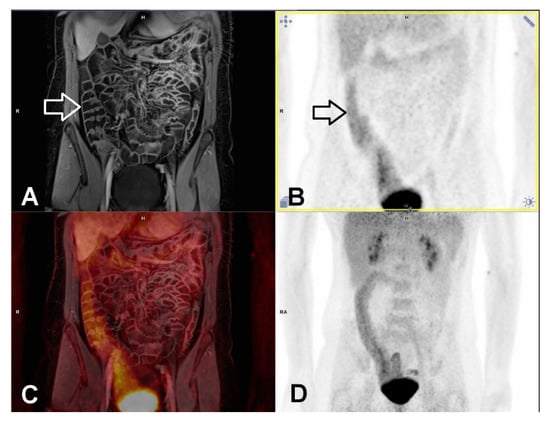

3.6. Extra-Intestinal Findings